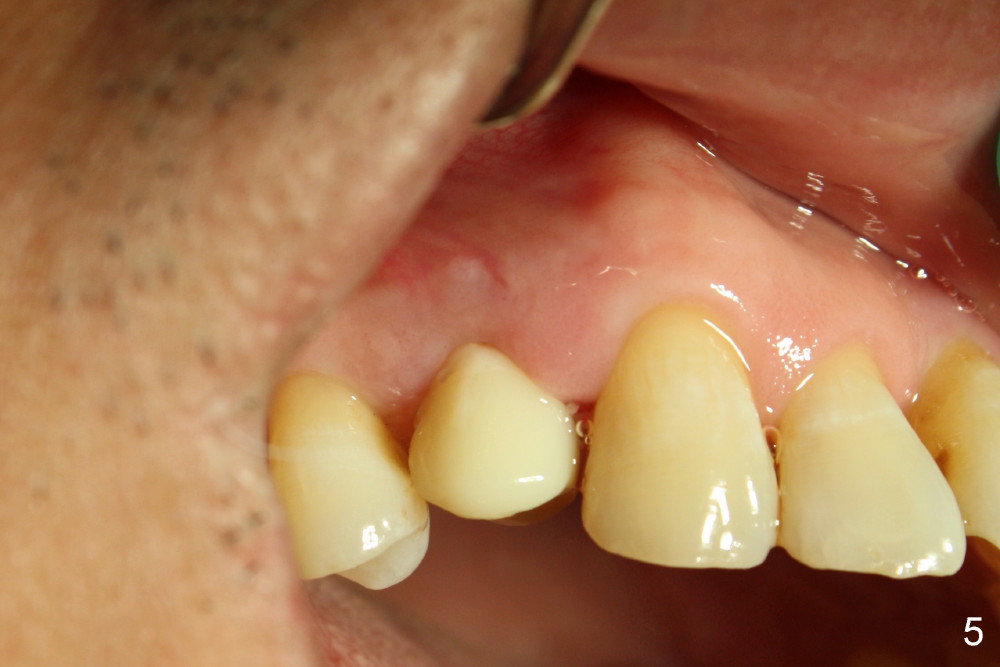

Five days later, the gingiva around the provisional returns to normal color (Fig.5,6, as compared to Fig.3,4). There is minimal postop pain in spite of difficult exodontia.

The patient returns 6 months postop for impression of a permanent restoration. The gingiva with knife-edged papillae adapts to the provisional (Fig.7). The gingiva looks healthy when the provisional is removed (Fig.8). The buccal bone resorption seems to be minimal, as compared to Fig.1,2. There is no bone loss between immediately postop (Fig.9 I; implant), 4.5 months postop (Fig.10 A: abutment), 4 and 7 months post cementation (Fig.11,12 C: crown). Soft and hard tissue morphology remains normal 7 months post cementation (Fig.13). No bone loss is observed 15 months post cementation (Fig.14). The papillae (Fig.15) and bone (Fig.16,17) remain stable 29 months post cementation.